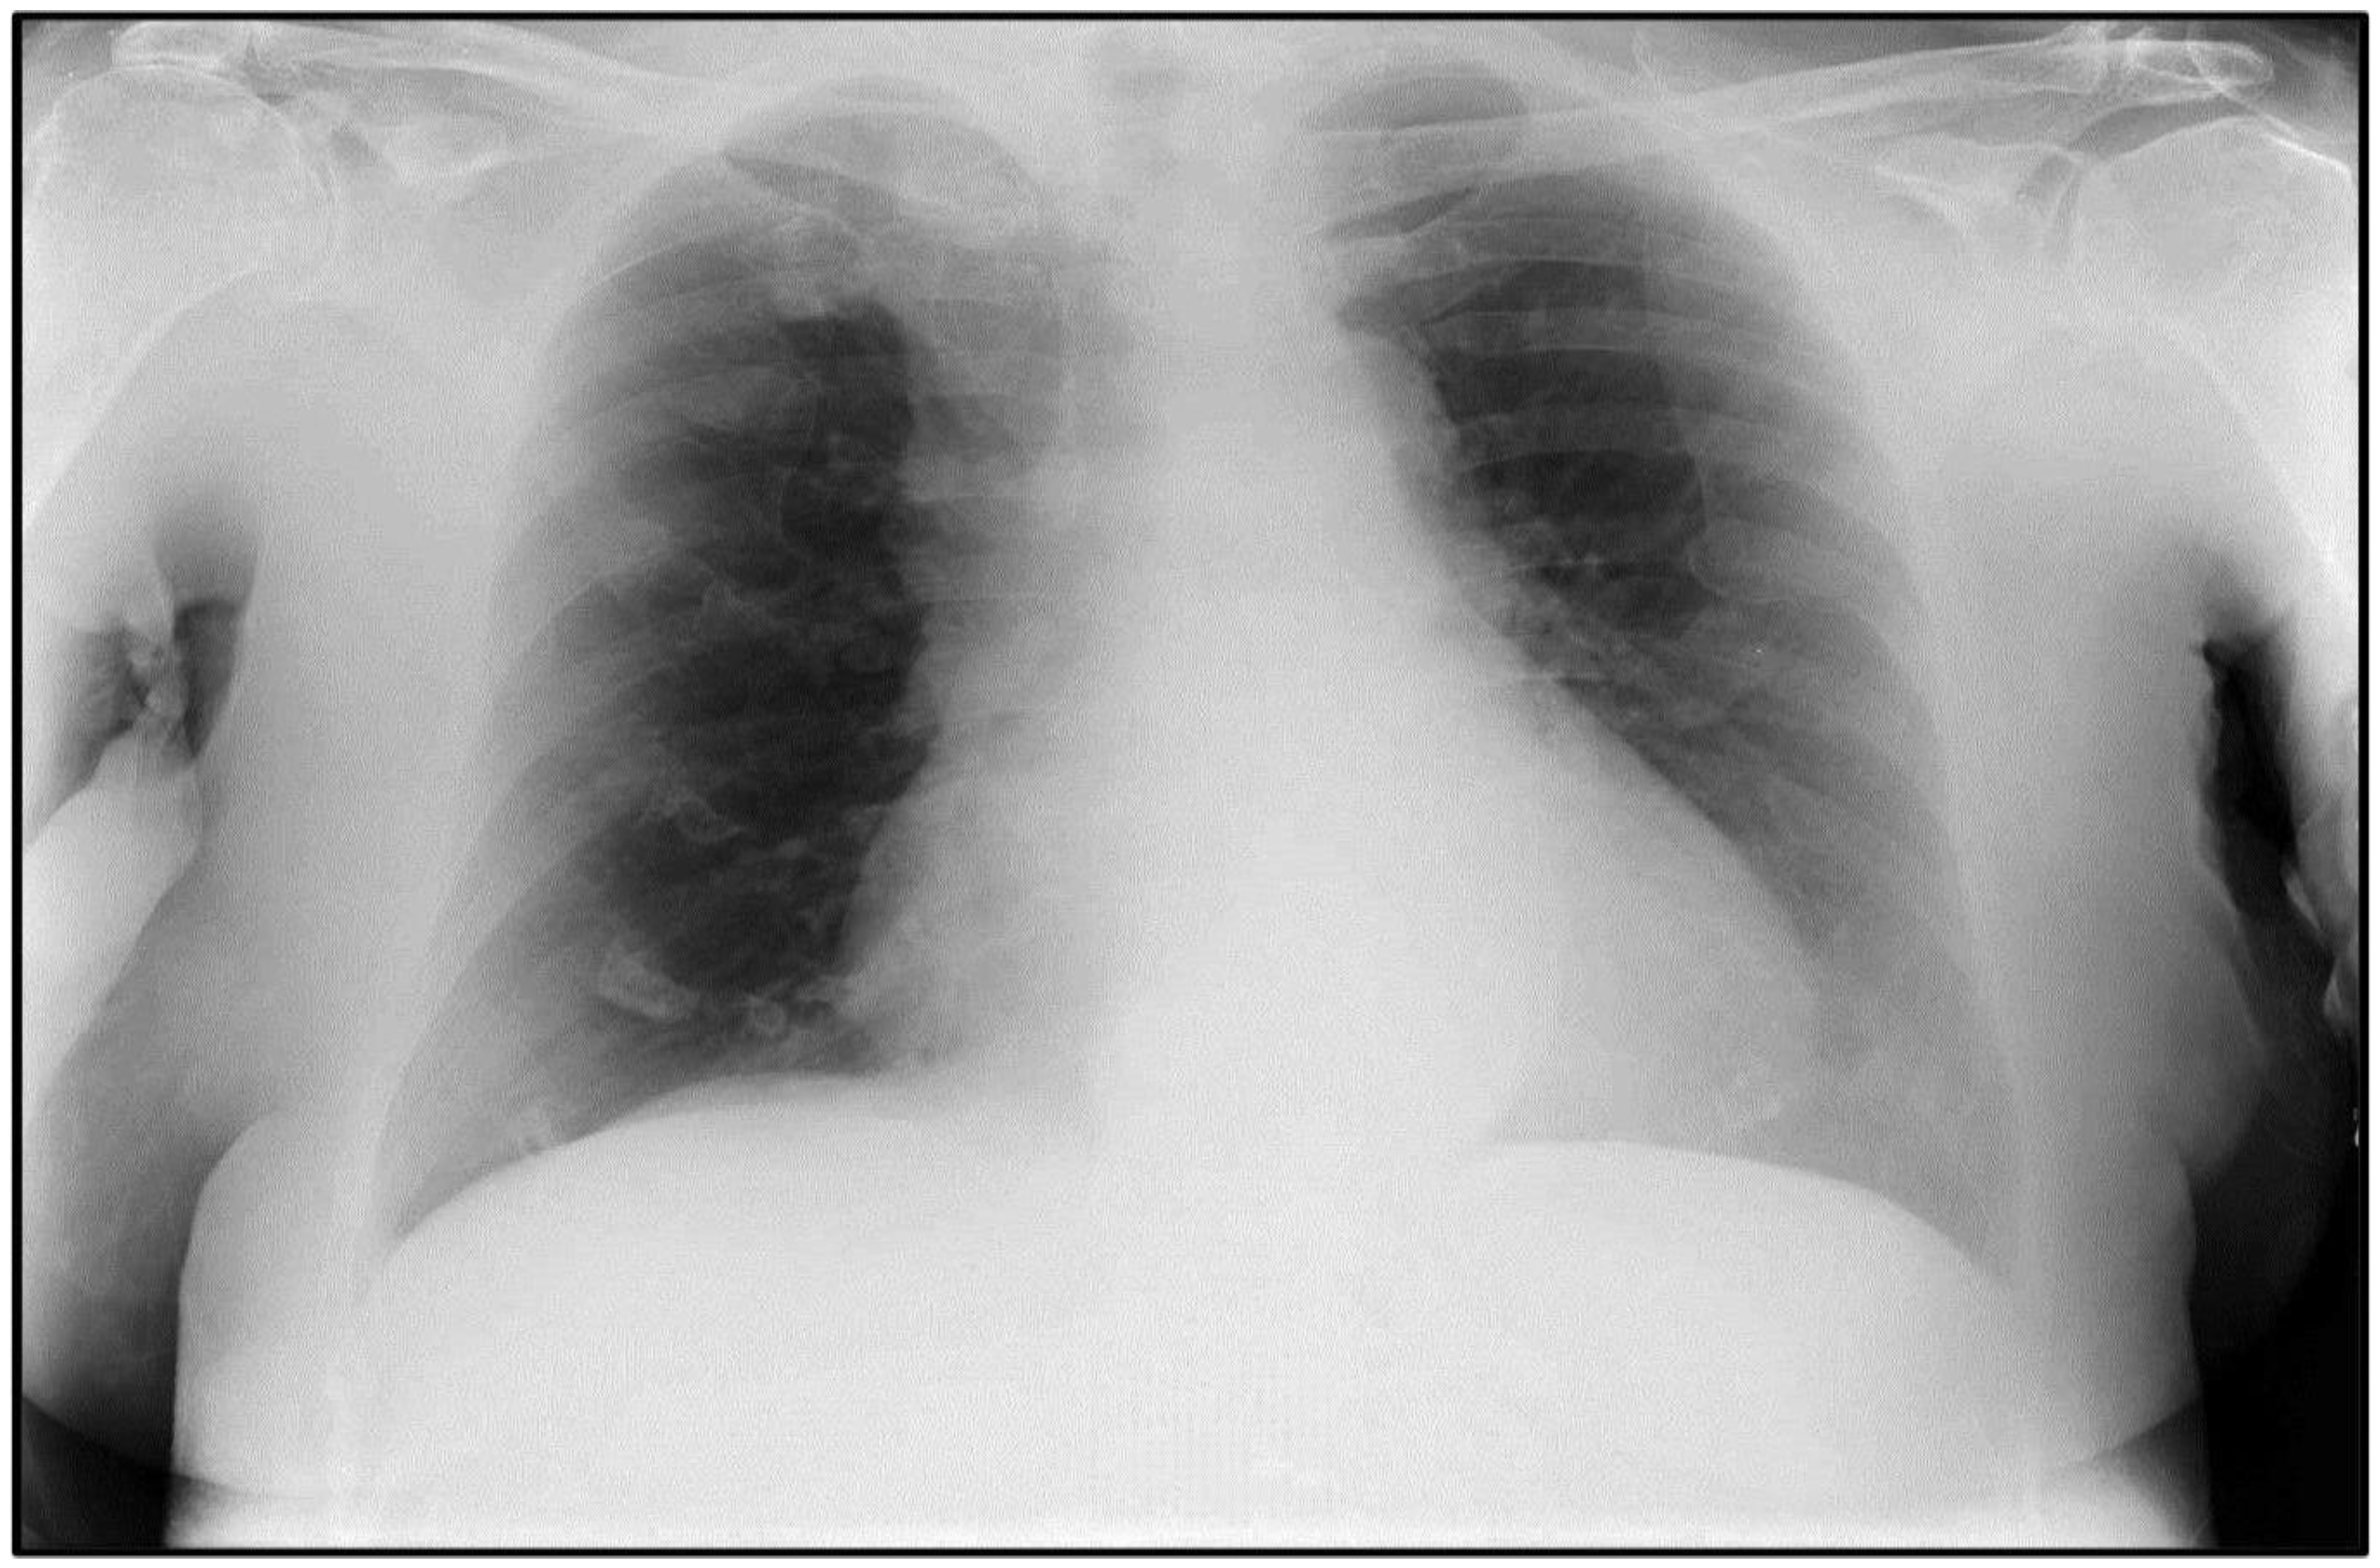

2.1. Case #1